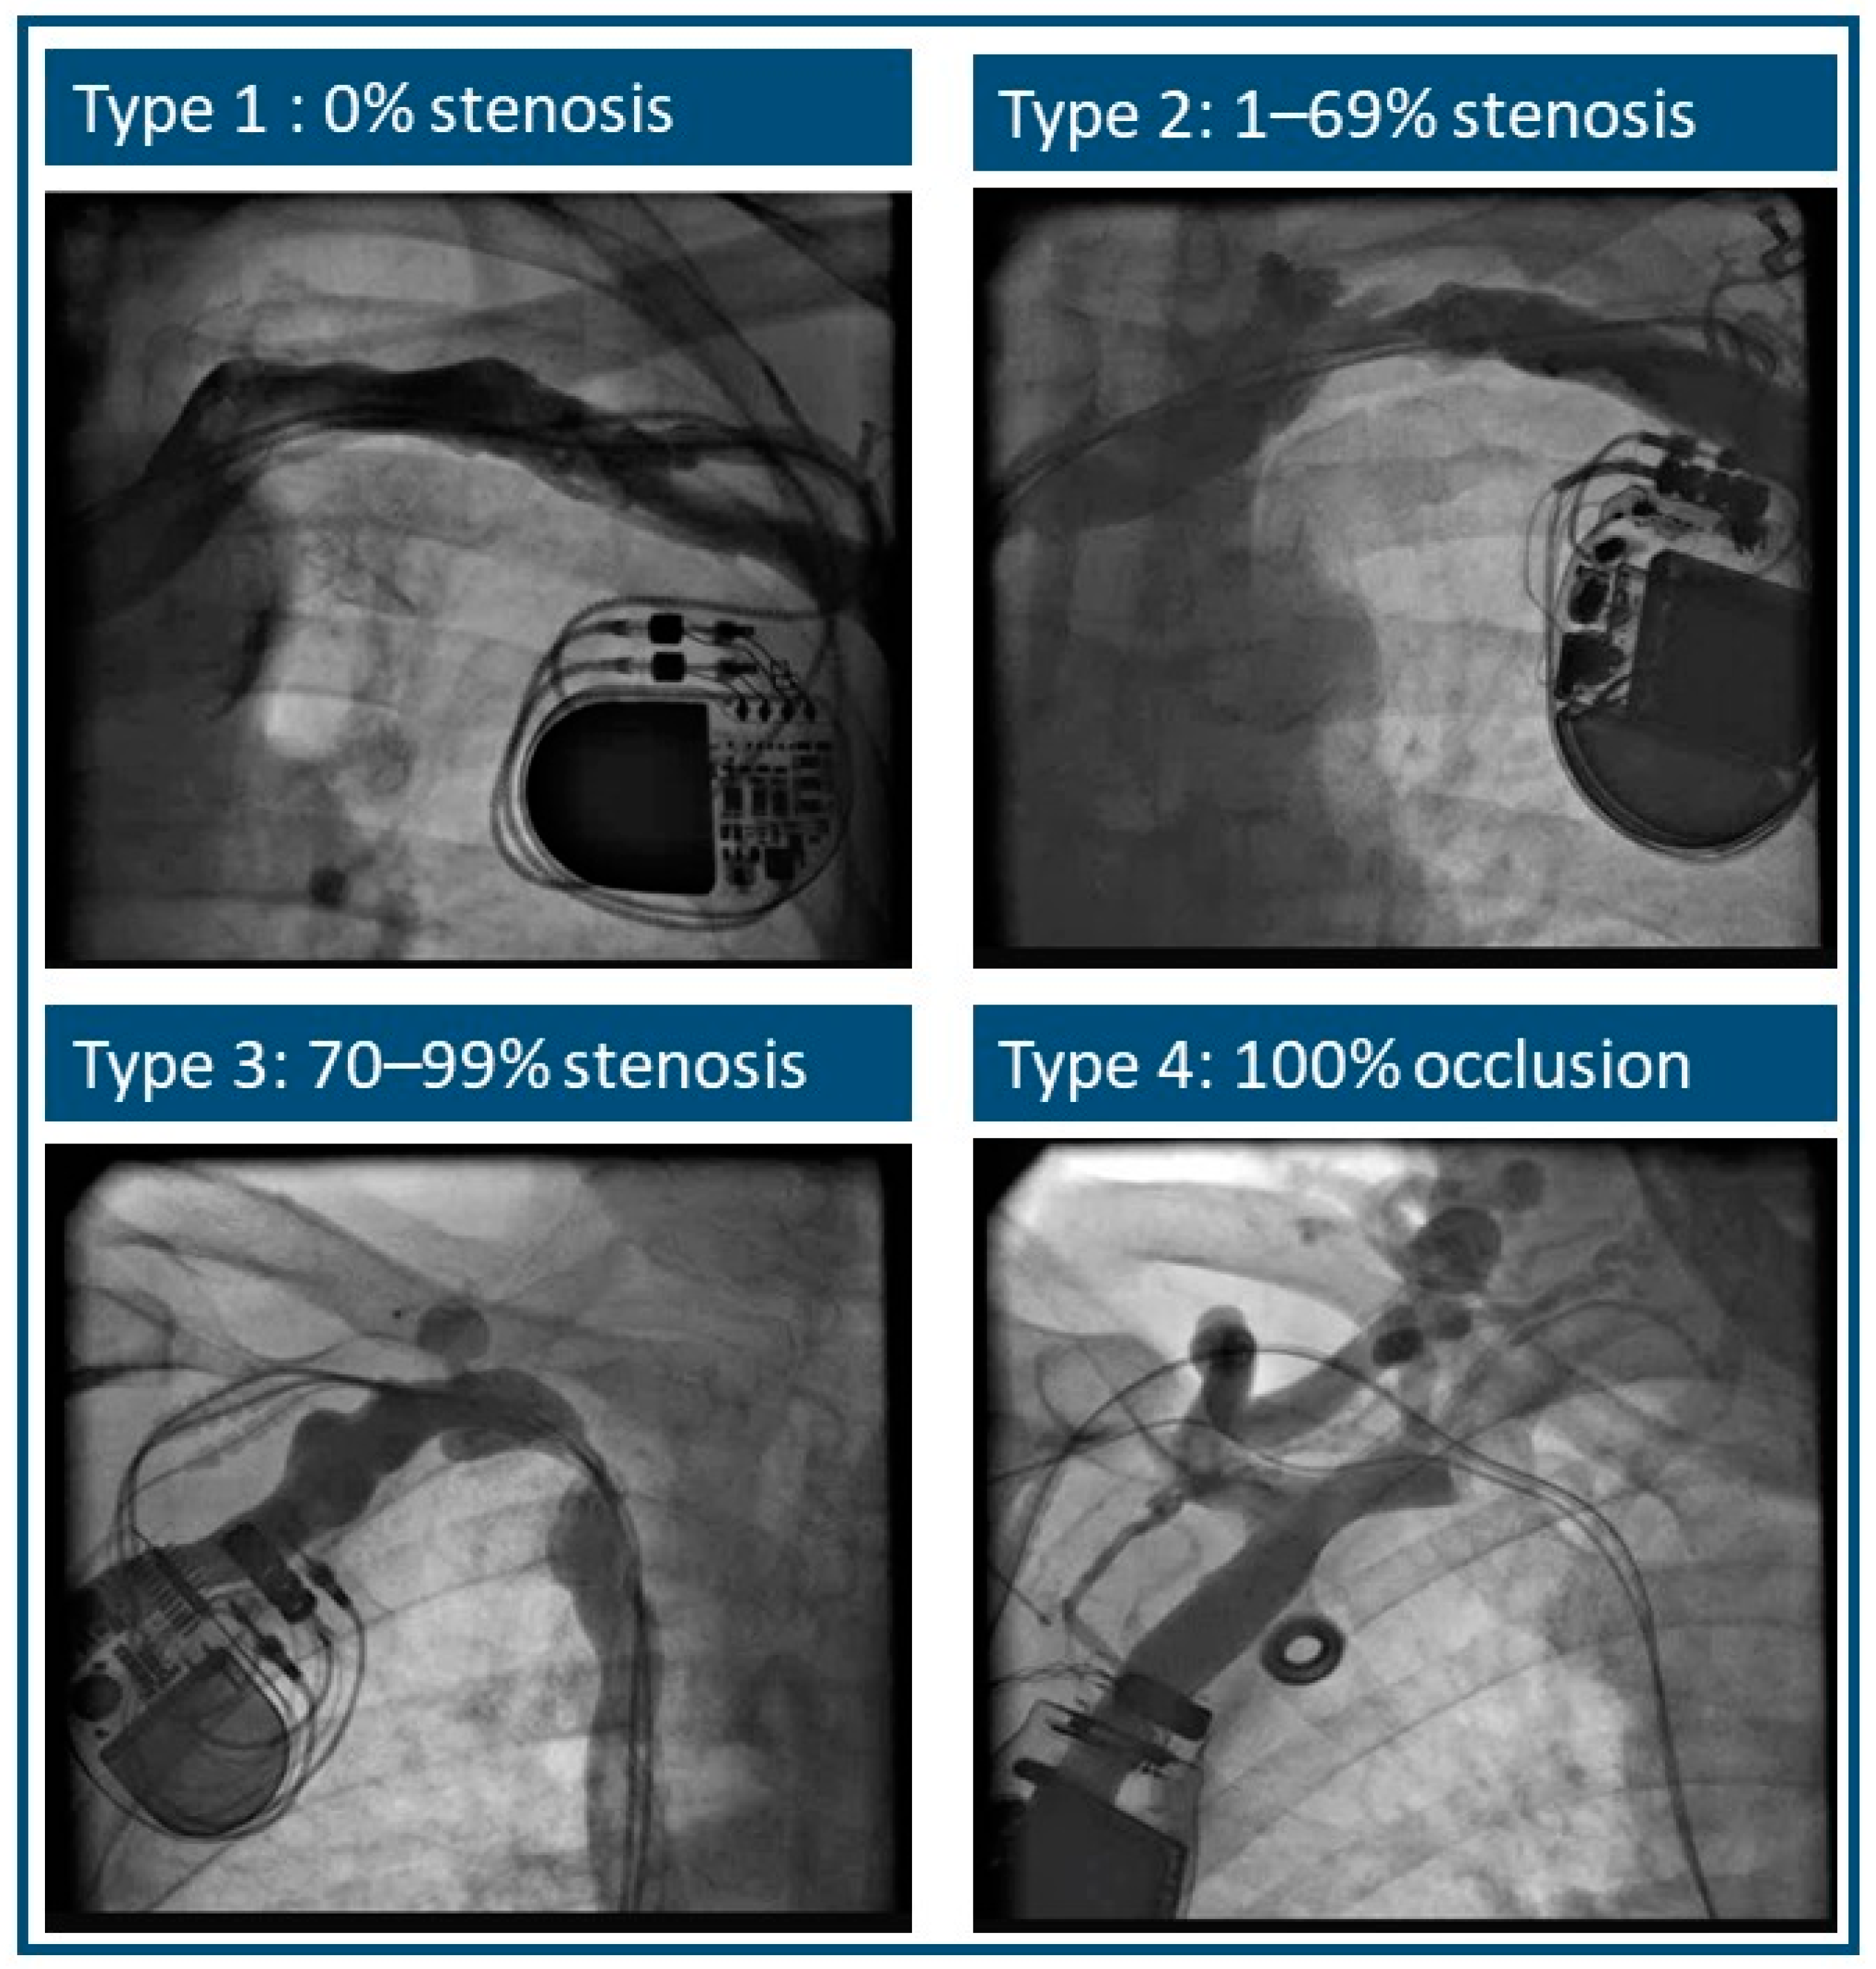

| Types of Stenosis | Cephalic Vein | Subclavian Vein | Total |

|---|---|---|---|

| 1 and 2 | 82 (92%) | 58 (79%) | 140 |

| 3 and 4 | 7 (8%) | 15 (21%) | 22 |

| total | 89 | 73 | 162 |

| Mean stenosis ration | ||

| 36 ± 13% | 46 ± 17% | |

| Types of stenosis | ||

| 1 (stenosis 0%) | 6 (6.7%) | 3 (4.1%) |

| 2 (stenosis 1–69%) | 76 (85.4%) | 55 (75.3% |

| 3 (stenosis 70–99%) | 3 (3.4%) | 9 (12.3%) |

| 4 (occlusion) | 4 (4.5%) | 6 (8.2%) |